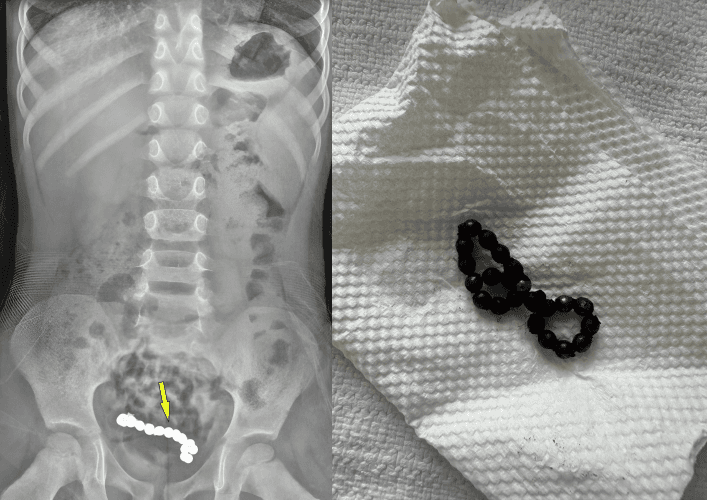

1년간 복통을 겪어온 4세 남아의 뱃속에서 자석 조각 22개가 발견되었습니다. 이 자석들은 서로 붙어있어 아이의 장 일부가 괴사하여 약 15cm를 절제하는 수술이 진행되었습니다.

오만에 거주하는 A군은 지속적인 복통으로 소하르병원 소아응급의학과를 방문했습니다. 복부 엑스레이와 컴퓨터단층촬영(CT) 결과, 하복부에서 사슬처럼 연결된 둥근 이물질이 관찰되었습니다.